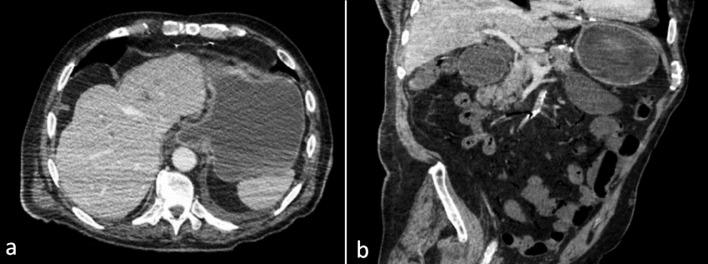

Acute Mesenteric Ischemia (AMI) is a rare life-threatening entity caused by sudden interruption of the blood supply to a segment of the bowel due to impairment of mesenteric arterial blood flow or venous drainage. Clinical presentation varies according to the time course of vascular occlusion. Contrast-enhanced Computed Tomography (CT) of the abdomen represents the main diagnostic test for AMI diagnosis, enabling fast and excellent evaluation of the intestine, mesenteric vasculature, and other ancillary characteristics of AMI. Typical CT findings of AMI include paralytic ileus, decreased or absent bowel wall contrast-enhancement, pneumatosis intestinalis, and porto-mesenteric venous gas. We hereby report a case of an 89-year-old man presenting with AMI due to Superior Mesenteric Artery (SMA) thrombotic occlusion following endovascular stenting superficial femoral arteries. Typical findings were observed on abdominal CT imaging, yet associated with the presence of gas exclusively in the SMA district, without any involvement of the porto-mesenteric venous system. Different imaging features and pitfalls can help radiologists to accurately diagnose AMI, especially when irreversible bowel damage is about to occur. Therefore, radiologists and emergency physicians should be aware of the unusual association between gas in the SMA arterial district and AMI, even in the absence of porto-mesenteric venous system involvement, in order to urge prompt surgical consultation when observed.

急性肠系膜缺血(AMI)是一种罕见的危及生命的病症,由肠系膜动脉血流或静脉引流受损导致肠段血液供应突然中断引起。临床表现根据血管闭塞的时间进程而有所不同。腹部增强计算机断层扫描(CT)是诊断AMI的主要检查方法,能够快速且出色地评估肠道、肠系膜血管系统以及AMI的其他辅助特征。AMI的典型CT表现包括麻痹性肠梗阻、肠壁强化减弱或消失、肠壁积气以及门静脉-肠系膜静脉积气。我们在此报告一例89岁男性患者,因股浅动脉血管内支架置入术后肠系膜上动脉(SMA)血栓形成闭塞而出现AMI。腹部CT成像观察到典型表现,但仅在SMA区域存在气体,门静脉-肠系膜静脉系统未受累。不同的影像学特征和陷阱有助于放射科医生准确诊断AMI,尤其是在即将发生不可逆肠损伤时。因此,放射科医生和急诊医生应意识到SMA动脉区域气体与AMI之间的异常关联,即使在门静脉-肠系膜静脉系统未受累的情况下,以便在观察到这种情况时促使及时进行外科会诊。